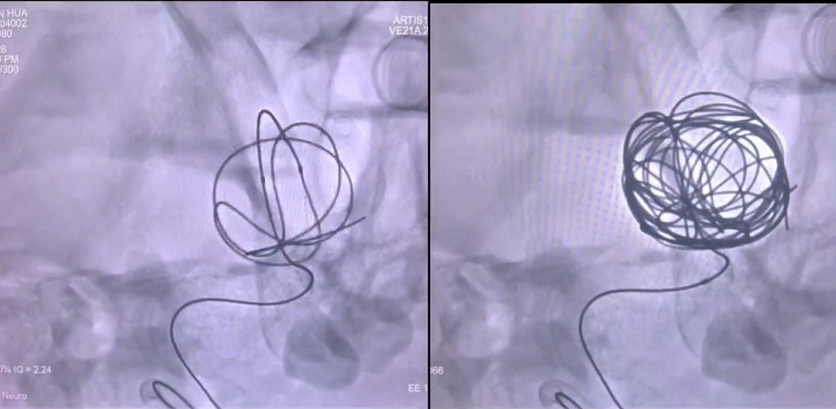

2. 植入密网,重塑通路

密网支架释放过程

DSA示动脉瘤基本不显影,载瘤动脉血流通畅